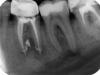

poma_puma Опубликовано 16 апреля, 2007 Автор Поделиться Опубликовано 16 апреля, 2007 Здравствуйте, это я вновь. Запломбировали мне каналы. Вот как это выглядит на картинке. Пока проблем нет, хожу с временной пломбой уже больше месяца.Иногда о себе дает знать соседний 7-ой зуб. Есть ли какие мнения от новой картины состояния моих зубов, буду признаетелен.Спасибо. Ссылка на комментарий

Штаматолог Опубликовано 16 апреля, 2007 Поделиться Опубликовано 16 апреля, 2007 Здравствуйте, это я вновь. Запломбировали мне каналы. Вот как это выглядит на картинке. Пока проблем нет, хожу с временной пломбой уже больше месяца. Иногда о себе дает знать соседний 7-ой зуб. Есть ли какие мнения от новой картины состояния моих зубов, буду признаетелен. Спасибо. то что прошли так хорошо каналы - это безусловно плюс, шансы наверное все-таки есть. Что по этому снимку не нравится лично мне: 1. в первую очередь конечно 7-ка, как и предполагалось там те же проблемы, начинайте лечить его тоже. 2. пародонтит между 6 и 7 а также 7 и 8. ну и если придираться : нависающая пломба на 8-ке и плохо пройденные медиальные каналы. и вот я не понял, что там на 6-ке у вас коронка? на дистальной стороне нет герметичности - устье канала контактирует с внешней средой. хотя конечно может это снимок был в процессе, а не окончательный. Ссылка на комментарий

конфьюзд Опубликовано 22 апреля, 2007 Поделиться Опубликовано 22 апреля, 2007 Здравствуйте, это я вновь. Запломбировали мне каналы. Вот как это выглядит на картинке. Пока проблем нет, хожу с временной пломбой уже больше месяца. Иногда о себе дает знать соседний 7-ой зуб. Есть ли какие мнения от новой картины состояния моих зубов, буду признаетелен. Спасибо. Просветите, пожалуйста, что это возле верхушек корней на снимке? Пломбировочный материал? Ссылка на комментарий

Doc Опубликовано 22 апреля, 2007 Поделиться Опубликовано 22 апреля, 2007 Просветите, пожалуйста, что это возле верхушек корней на снимке? Пломбировочный материал? Именно он, выведенный далеко за верхушку. Раньше был такой метод лечения гранулем. Забыл фамилию докторицы, она сейчас в Москве это открытие пропагандирует. Рассказывает, что вакуумом выжигает кисту, а потом заполняет по самое не могу пастой. Говорит, что хороший способ. Многие верят. Ссылка на комментарий